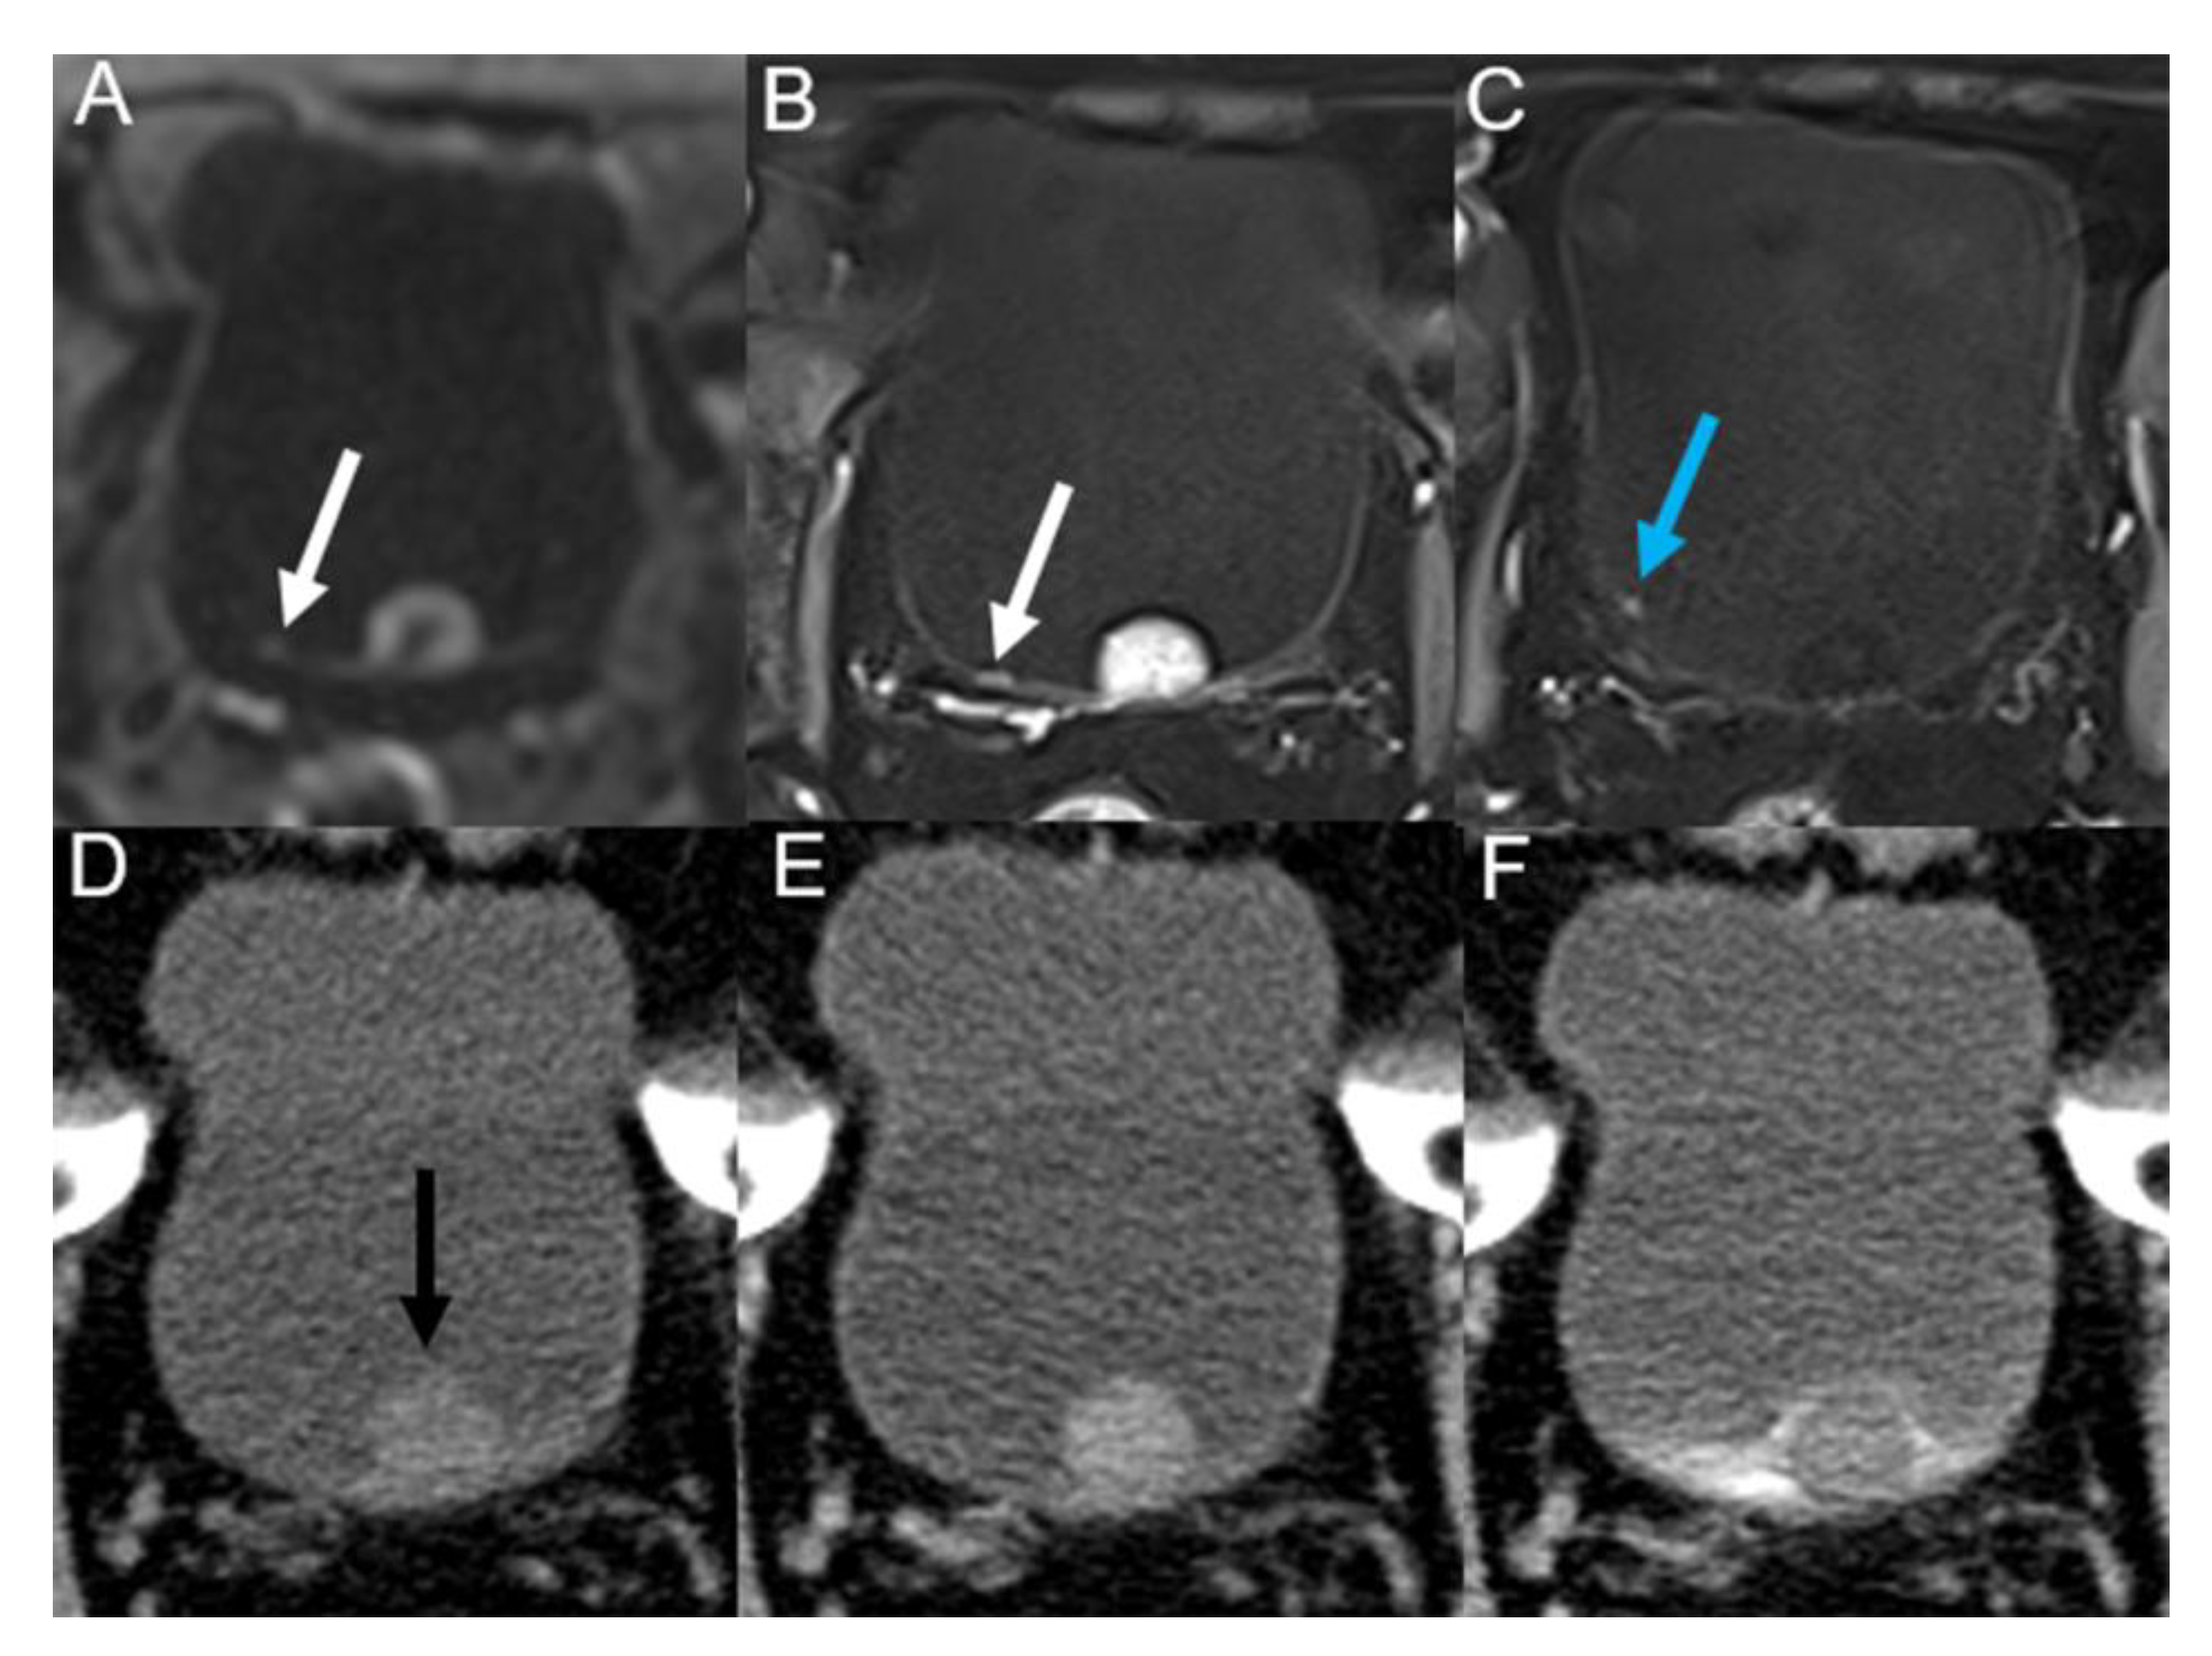

| Morphological Classification | MRI | MDCT |

|---|---|---|

| Nodular masses | 100% (38/38) | 92.1% (35/38) |

| Irregular wall thickening | 90.0% (9/10) | 30.0% (3/10) |

| Smooth wall thickening | 25.0% (2/8) | 0% (0/8) |